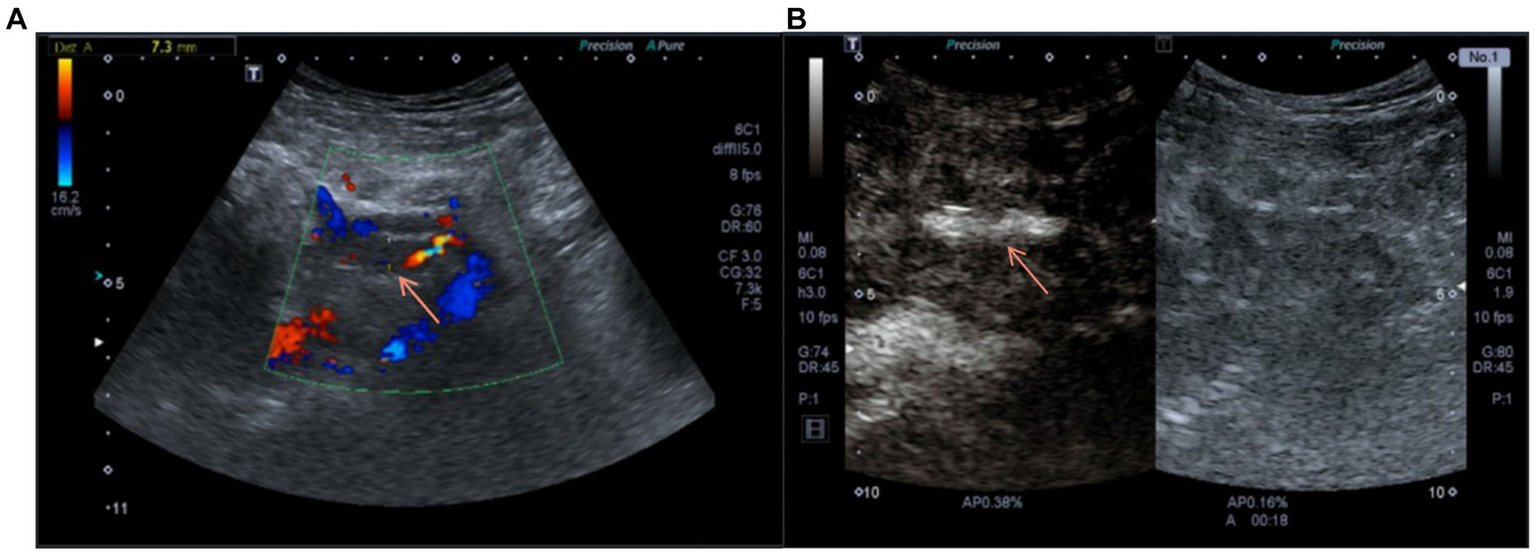

To further confirm the diagnosis, we performed contrast-enhanced ultrasonography on the patient, which showed that within the transplant renal artery Vmax = 62 cm/s, with a prolonged resistance acceleration time. There is a filling defect with non-enhancing hypoechoic mass of approximately 45 mm × 8 mm in size with in the renal vein lumen, which led to a maximum venous stenosis of >70% (Figures 2A,B). In response to allograft venous thrombosis, we worked with interventional radiologists to assess the condition to formulate a treatment plan using anti-coagulation therapy.

Figure 2

(A) Doppler ultrasound on admission suggested the blood flow of the transplanted renal vein was blocked. (B) Contrast-enhanced ultrasound before anticoagulation showed the contrast agent passing through the transplanted renal vein.